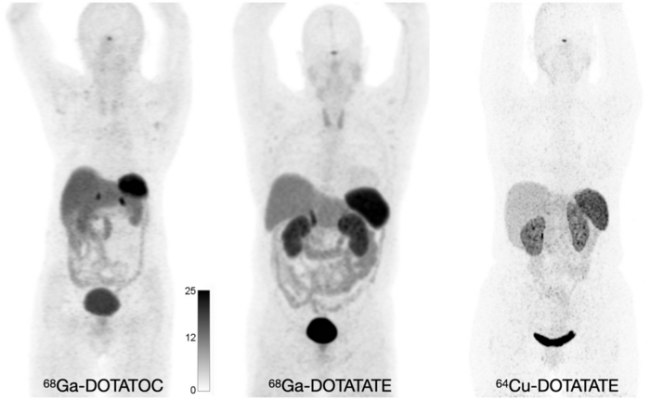

Normal biodistribution of 68Ga-DOTATOC, 68Ga-DOTATATE, and 64Cu-DOTATATE. Image courtesy of Hope TA, Allen-Auerbach M, Bodei L, Calais J, et al., SNMMI Procedure Standard/EANM Practice Guideline for SSTR PET: Imaging Neuroendocrine Tumors. J Nucl Med. 2023 Feb;64(2):204-210.

SSTRs are overexpressed on a wide range of NET cells and can be targeted using somatostatin analogs (SSAs). While SSAs were initially targeted with 111In-pentetreotide scintigraphic imaging, the next generation of SSTR PET imaging with 68Ga-DOTATATE, 68Ga-DOTATOC, or 64Cu-DOTATATE, allows for improved sensitivity of lesion detection, lower radiation dose, and shorter and more convenient study duration. The new standard/guideline focuses on these PET radiotracers.